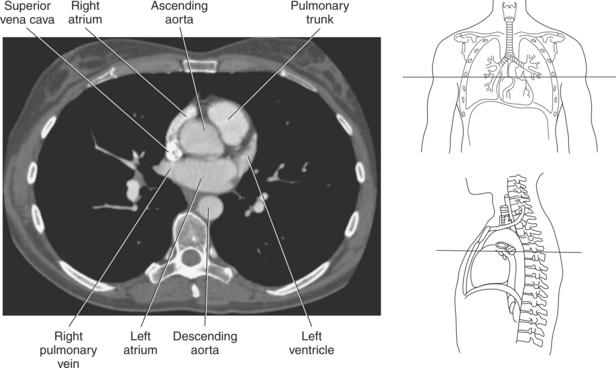

The right atrium forms the right border of the heart and receives deoxygenated blood from the body via the superior and inferior venae cavae and from the coronary sinus and cardiac veins that drain the myocardium. A small muscular embryonic appendage, the right auricle, projects upward and toward the left from the right atrium, covering the root of the aorta (Figure 6.40). The right ventricle lies on the diaphragm and comprises the largest portion of the anterior surface of the heart. It receives deoxygenated blood from the right atrium and forces it into the pulmonary trunk for conveyance to the lungs. Projecting off the inferior surface of the ventricular walls are conical-shaped projections of cardiac muscle called papillary muscles that anchor the cusps of the tricuspid valve to the right ventricle (Figure 6.39). The left atrium lies posterior to the right atrium and is the most posterior surface of the heart. It also has an embryonic appendage, the left auricle, that projects to the left of the pulmonary trunk over the superior surface of the heart. The left atrium receives oxygenated blood directly from the lungs via the four pulmonary veins (two on each side). The left ventricle forms the apex, left border, and most of the inferior surface of the heart. It receives oxygenated blood from the left atrium and pumps it into the aorta for distribution throughout the systemic circuit. The myocardium of the left ventricle is normally three times thicker than that of the right ventricle, reflecting the force necessary to pump blood to the distant sites of the systemic circulation (Figures 6.41 through 6.52). Two papillary muscles project from the ventricular walls to anchor the bicuspid valve to the ventricle (Figures 6.39 and 6.47).

Figure 6.43 Axial, T1-weighted MR scan of left atrium.

Key: RV, Right ventricle; LV, left ventricle; LA, left atrium; RA, right atrium.

Blood travels to and from the heart through the great vessels, which include the aorta, pulmonary arteries and veins, and superior and inferior venae cavae (Figures 6.54 and 6.55). The aorta is the largest artery of the body and can be divided into the ascending aorta, aortic arch, and descending aorta. The ascending aorta begins at the base of the left ventricle at the level of the sternal angle, then curves superiorly and posteriorly as the aortic arch over the root of the left lung. The top of the aortic arch is approximately at T3 (Figures 6.56 and 6.57). The arch continues as the descending aorta posterior to the left bronchus and pulmonary trunk, on the left side of the vertebral body of T4 (Figures 6.58 and 6.59). The descending aorta passes slightly anterior and to the left of the vertebral column as it descends through the thoracic and abdominal cavities (Figure 6.60). While in the thoracic cavity, the descending aorta is commonly called the thoracic aorta, and while in the abdominal cavity, it is called the abdominal aorta. The pulmonary trunk is the origin of the right and left pulmonary arteries and lies entirely within the pericardial sac. It arises from the right ventricle and ascends in front of the ascending aorta, courses posteriorly and to the left, where it bifurcates at the level of the sternal angle (T4) into the right and left pulmonary arteries (Figures 6.61 through 6.63). The pulmonary trunk is attached to the aortic arch by a fibrous cord called the ligamentum arteriosum, the remnant of an important fetal blood vessel (ductus arteriosus) that links the pulmonary and systemic circuits during fetal development (Figures 6.54 and 6.61). The right pulmonary artery courses laterally, posterior to the ascending aorta and superior vena cava, and anterior to the esophagus and right mainstem bronchus, to the hilum of the right lung. At the root of the right lung, the right pulmonary artery divides into two branches, with the lower branch supplying the middle and inferior lobes and the upper branch supplying the superior lobe (Figures 6.61 through 6.64). The left pulmonary artery, shorter and smaller than the right, is also the most superior of the pulmonary vessels. It travels horizontally, arching over the left mainstem bronchus, and enters the hilum of the left lung just superior to the left mainstem bronchus (Figures 6.61 through 6.64). Within the lungs, each pulmonary artery descends posterolateral to the main bronchus and divides into lobar and segmental arteries, continuing to branch out and to follow along with the smallest divisions of the bronchial tree (Figures 6.61 and 6.64). Located inferior to the pulmonary arteries are the four pulmonary veins, two each (superior and inferior) extending from each lung to enter the left atrium (Figures 6.54, 6.55, 6.61, and 6.64 through 6.68). They commence in a capillary network along the walls of the alveoli, where they are continuous with the capillaries of the pulmonary arteries. The venous capillaries merge to form small vessels that unite successively to eventually form a single trunk for each lobe: three for the right and two for the left lung. Frequently the trunk from the middle lobe of the right lung unites with the trunk from the upper lobe, forming just two trunks on the right side prior to entering the left atrium. The right superior pulmonary vein collects blood from the upper lobe segments of the right lung and passes anterior and inferior to the right pulmonary artery, behind the superior vena cava. The right inferior pulmonary vein receives blood from the right lower lobes of the lung and crosses behind the right atrium to the left atrium (Figures 6.61 and 6.69 through 6.71). The left superior pulmonary vein receives blood from the left upper lobe of the left lung and courses anterior and inferior to the left main bronchus as it enters the left atrium. The left inferior pulmonary vein drains the inferior lobe of the left lung and passes toward the left atrium anterior to the bronchi (Figures 6.61 and 6.72 through 6.74). The pulmonary veins course more horizontally than the pulmonary arteries and are ultimately oriented toward the left atrium. At the root of the lungs, the pulmonary veins are anterior to the pulmonary arteries, which are anterior to the bronchus. While within the lungs, the branches of the pulmonary arteries are anterior to the bronchi, which are anterior to the pulmonary veins. The superior and inferior venae cavae are the largest veins of the body. The superior vena cava is formed by the junction of the brachiocephalic veins, posterior to the right first costal cartilage, and carries blood from the thorax, upper limbs, head, and neck (Figure 6.24). As it travels inferiorly, it is located posterior and lateral to the ascending aorta before entering the upper portion of the right atrium (Figures 6.54 through 6.59). The inferior vena cava is formed by the junction of the common iliac veins in the pelvis and ascends the abdomen to the right of the abdominal aorta and anterior to the vertebral column. It passes through the caval hiatus of the diaphragm and almost immediately enters the inferior portion of the right atrium (Figures 6.75 and 6.76).